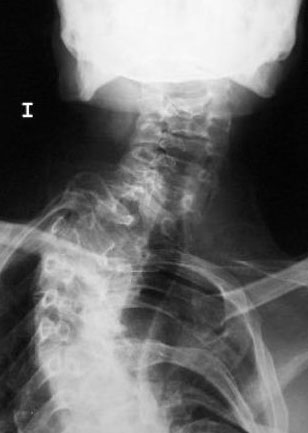

Artrosis cervical.

Artrosis cervical

APR Cervicoartrosis